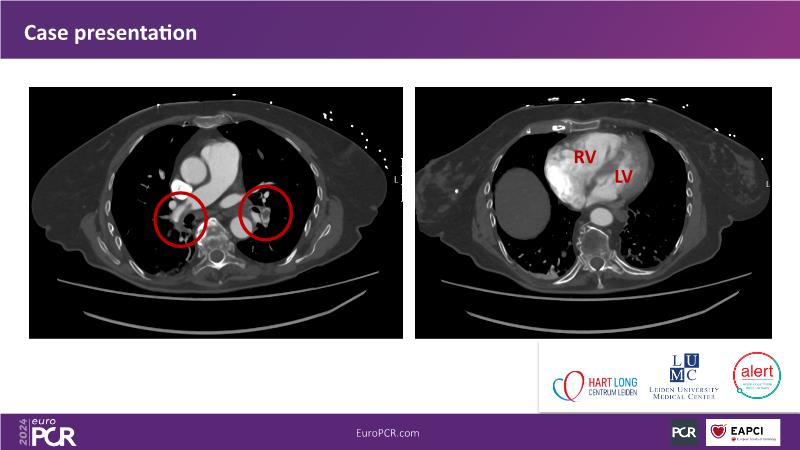

Advancing percutaneous treatment of pulmonary embolism with computer-assisted vacuum thrombectomy

Join this session to delve into innovations in computer-assisted vacuum thrombectomy for acute pulmonary embolism, leveraging real-life case scenarios to share practical experiences and discuss treatment strategies. Amidst the current surge in scientific research, ongoing trials like STORM PE and STRIKE PE are pivotal in shaping the landscape of pulmonary embolism management.